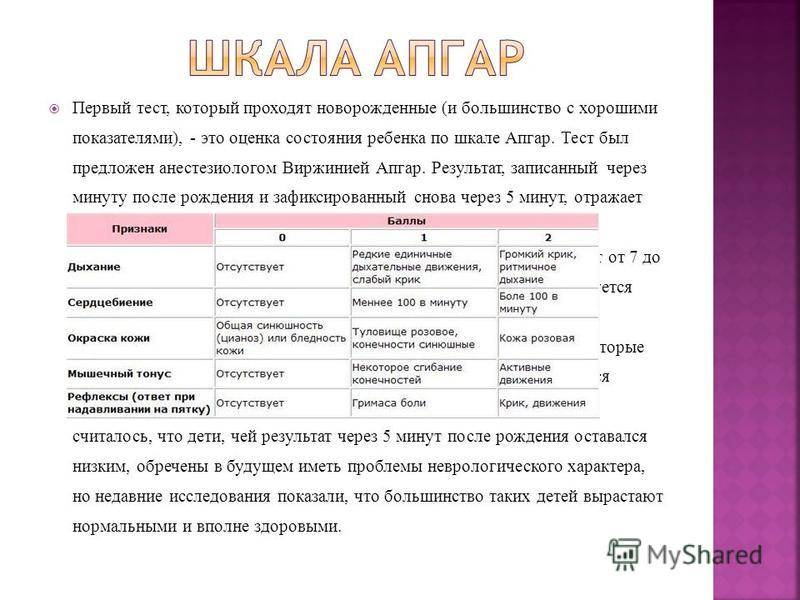

Шкала Апгар: что считать нормой для новорожденных